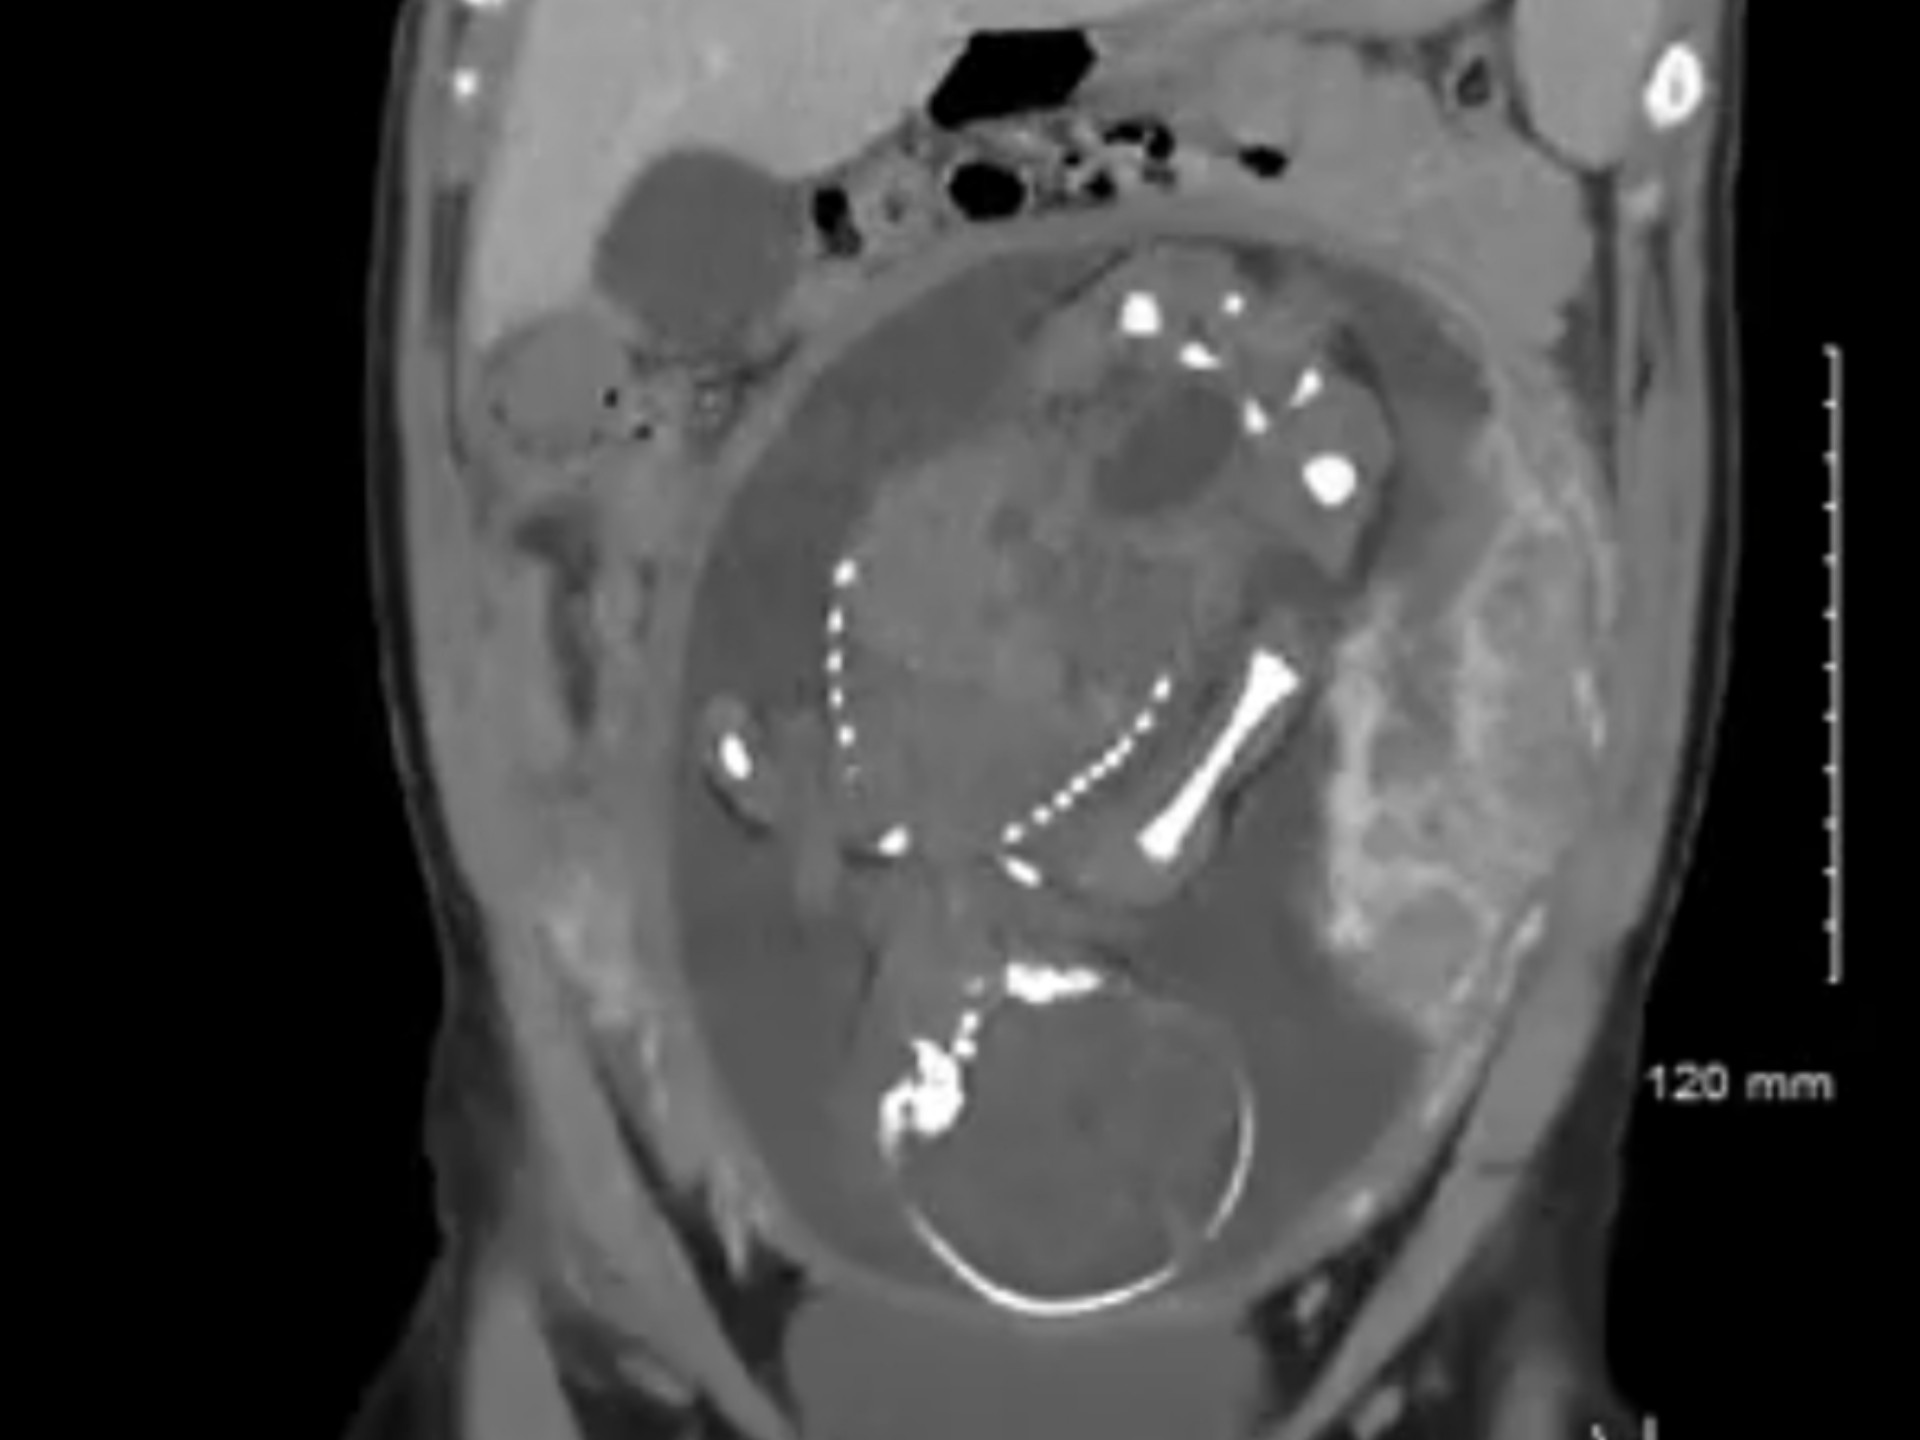

كيف يكون التهاب الزائدة الدودية في بطن الحامل؟

وضع الجنين غير طبيعي، الطبيب يستخدم يديه لإعادة الوضع إلى طبيعته.